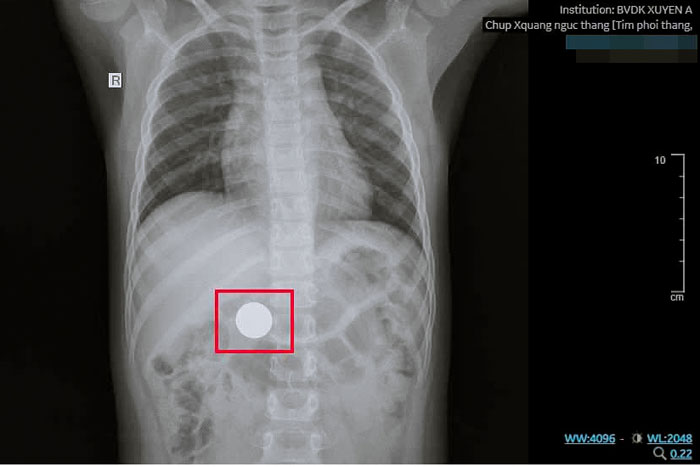

| Các bác sĩ Khoa Nội soi BVĐK Xuyên Á Vĩnh Long gắp dị vật đồng xu do bé trai 6 tuổi vô tình nuốt. |

Đơn cử, trong lúc vui chơi, bé trai 6 tuổi (ngụ tỉnh Vĩnh Long) vô tình nuốt phải đồng xu kim loại dạng thẻ game. Gia đình phát hiện và lập tức đưa bé đến bệnh viện cấp cứu. Các bác sĩ nhanh chóng thăm khám và chỉ định chụp X-quang.

Bệnh nhi được chuyển đến Khoa Nội soi, tiến hành nội soi dạ dày dưới gây mê, sử dụng dụng cụ chuyên dụng để tiếp cận và gắp DV- là đồng xu đường kính 22mm đã được lấy ra an toàn. Kiểm tra niêm mạc dạ dày- thực quản cho thấy không có tổn thương, trầy xước hay chảy máu. Bé tỉnh táo, sức khỏe ổn định và được xuất viện trong ngày.

BS Lê Vũ Trường- Khoa Nội soi BVĐK Xuyên Á Vĩnh Long cho biết: “Bé rất may mắn vì được gia đình đưa đến bệnh viện kịp thời và DV không phải vật sắc nhọn nên không gây tổn thương đường tiêu hóa. Song, nếu để lâu, đồng xu có thể kẹt lại ở một đoạn ruột, gây tắc ruột và ảnh hưởng nghiêm trọng đến sức khỏe của bé”.